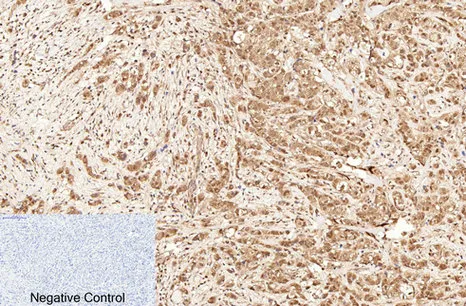

Cleaved-Caspase-9 p35 (D315) Rabbit Polyclonal Antibody

Cat: APRab08971

Cleaved-Caspase-8 (D384) Rabbit Polyclonal Antibody

Cat: APRab08968